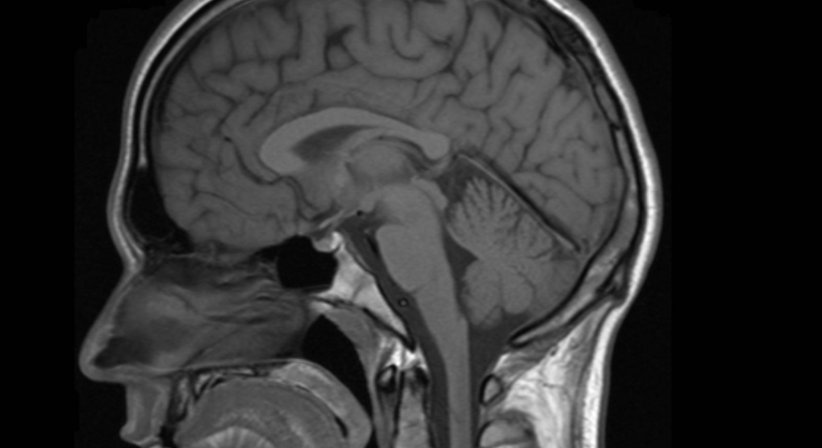

Die Magnetresonanztomographie funktioniert auf der Basis von elektromagnetischen Impulsen (ähnlich den herkömmlichen Radiowellen). Durch diese werden im Körper befindliche Wasserstoffkerne, die in den verschiedenen Geweben unterschiedlich dicht anzutreffen sind, zu einer kurzen Bewegung angeregt, die dann wiederum mittels sehr sensibler Sensoren gemessen werden kann. Die gesammelten Daten werden mittels Computer in Schnittbilder umgerechnet.

Die hohen Kosten der Untersuchung wird durch eine herausragende Bildqualität und einen hohen diagnostischen Wert gerechtfertigt. Durch die Verabreichung von speziellem Kontrastmittel kann die Aussagekraft der Untersuchung noch gesteigert werden. Besonders im neurologischen Bereich, also zur Beurteilung des Gehirnes, ist diese Methode unübertroffen, im Brustraum aber liefert beispielsweise die CT mehr Information.